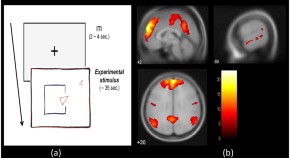

Rodents have an orientation map of their surroundings, produced and updated by a network of neurons in the entorhinal cortex known as 'grid cells'. However, it is currently unknown whether humans encode their location in a similar manner. Using functional magnetic resonance imaging in humans, a macroscopic signal representing a subject's position in a virtual reality environment is now detected that meets the criteria for defining grid-cell encoding.